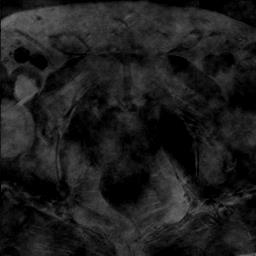

Modern deep neural networks struggle to transfer knowledge and generalize across diverse domains when deployed to real-world applications. Currently, domain generalization (DG) is introduced to learn a universal representation from multiple domains to improve the network generalization ability on unseen domains. However, previous DG methods only focus on the data-level consistency scheme without considering the synergistic regularization among different consistency schemes. In this paper, we present a novel Hierarchical Consistency framework for Domain Generalization (HCDG) by integrating Extrinsic Consistency and Intrinsic Consistency synergistically. Particularly, for the Extrinsic Consistency, we leverage the knowledge across multiple source domains to enforce data-level consistency. To better enhance such consistency, we design a novel Amplitude Gaussian-mixing strategy into Fourier-based data augmentation called DomainUp. For the Intrinsic Consistency, we perform task-level consistency for the same instance under the dual-task scenario. We evaluate the proposed HCDG framework on two medical image segmentation tasks, i.e., optic cup/disc segmentation on fundus images and prostate MRI segmentation. Extensive experimental results manifest the effectiveness and versatility of our HCDG framework.